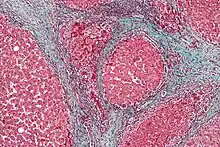

Once the biopsy is obtained, a pathologist will study the sample. Cirrhosis is defined by its features on microscopy: (1) the presence of regenerating nodules of hepatocytes and (2) the presence of fibrosis, or the deposition of connective tissue between these nodules. The pattern of fibrosis seen can depend on the underlying insult that led to cirrhosis. Fibrosis can also proliferate even if the underlying process that caused it has resolved or ceased. The fibrosis in cirrhosis can lead to destruction of other normal tissues in the liver: including the sinusoids, the space of Disse, and other vascular structures, which leads to altered resistance to blood flow in the liver, and portal hypertension.[81]

Histopathology of steatohepatitis with moderate fibrosis, with thin fibrous bridges (Van Gieson's stain)[82].jpg.webp) Histopathology of steatohepatitis with established cirrhosis, with thick bands of fibrosis (Van Gieson's stain)[82]

Histopathology of steatohepatitis with established cirrhosis, with thick bands of fibrosis (Van Gieson's stain)[82]_(5690946257).jpg.webp) Trichrome stain, showing cirrhosis as a nodular texture surrounded by fibrosis (wherein collagen is stained blue).

Trichrome stain, showing cirrhosis as a nodular texture surrounded by fibrosis (wherein collagen is stained blue).

As cirrhosis can be caused by many different entities which injure the liver in different ways, cause-specific abnormalities may be seen. For example, in chronic hepatitis B, there is infiltration of the liver parenchyma with lymphocytes.[81] In congestive hepatopathy there are erythrocytes and a greater amount of fibrosis in the tissue surrounding the hepatic veins.[83] In primary biliary cholangitis, there is fibrosis around the bile duct, the presence of granulomas and pooling of bile.[84] Lastly in alcoholic cirrhosis, there is infiltration of the liver with neutrophils.[81]